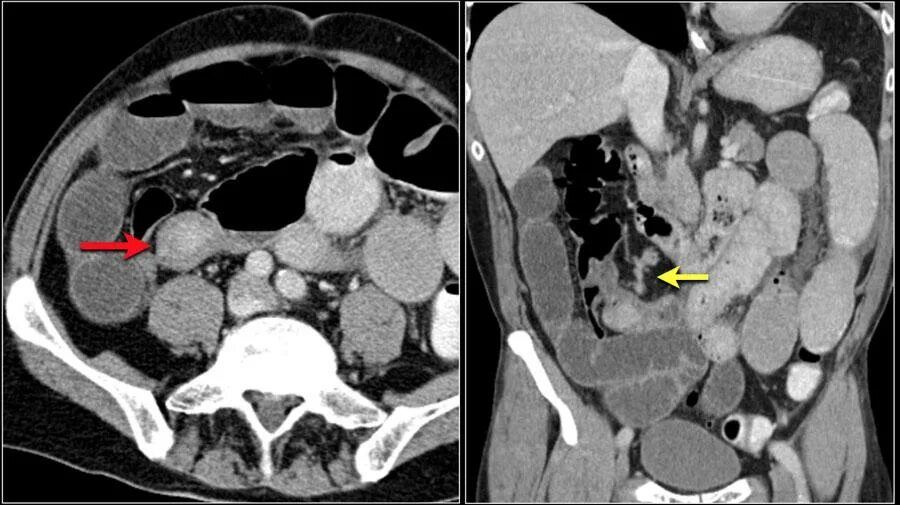

Рак прямой кт